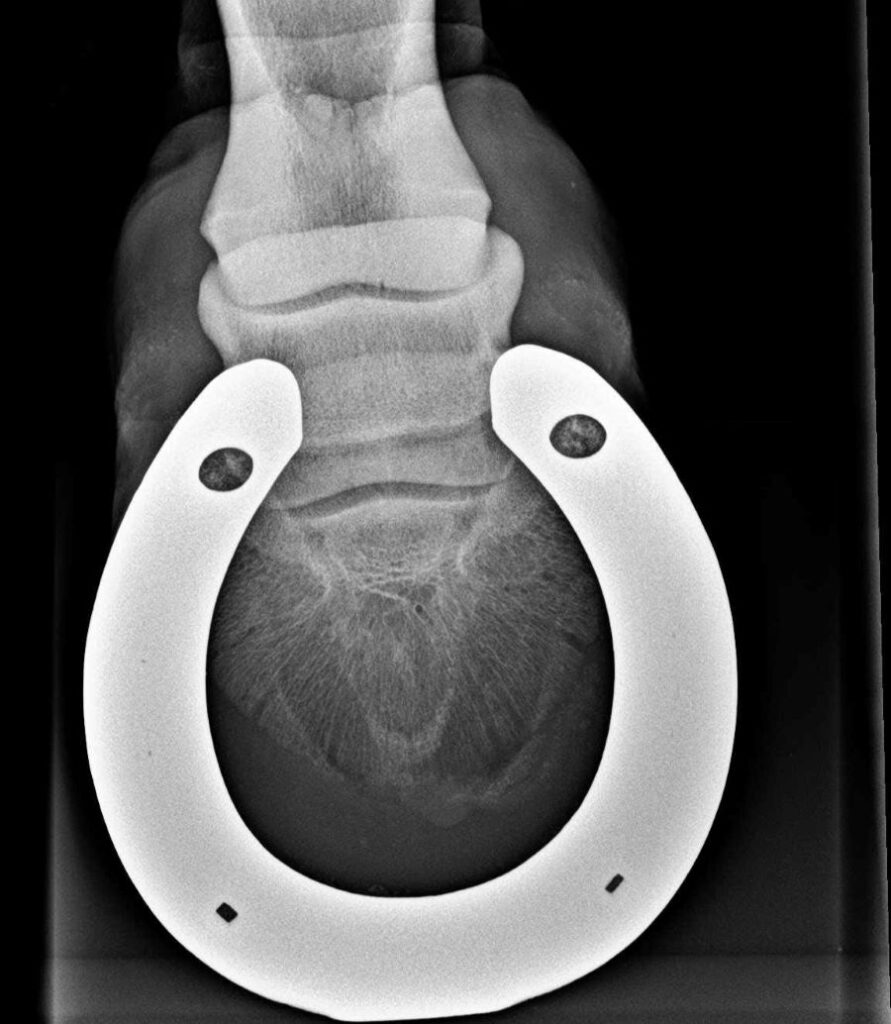

Wenn dein Pferd Hufeisen hat, ist es sehr ratsam, diese vor dem Röntgen von deinem Hufprofi abnehmen zu lassen. Ein Hufeisen auf dem Röntgenbild ist wie ein massiver Balken vor der Aussicht. Das Metall verursacht starke Streustrahlung, das Bild wird um das Eisen herum unscharf oder überbelichtet und natürlich verdeckt das Eisen auch Teile der relevanten Strukturen. Feine Details wie Haarrisse können so übersehen werden, der Hufbeinrand oder Teile des Strahlbeins werden verdeckt. Zudem verfälscht der Beschlag die Beurteilung der Sohlendicke. Für eine verlässliche Diagnose führt daher kein Weg daran vorbei: Das Eisen muss runter.